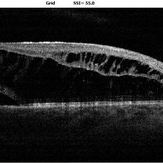

Optic Disc Pit Optic Disc PitOct 8 2019 by DIEGO TOLENTINO OCT of a patient with optic disc pit. Photographer: Diego Tolentino Condition/keywords: optic disc pit, optical coherence tomography (OCT)